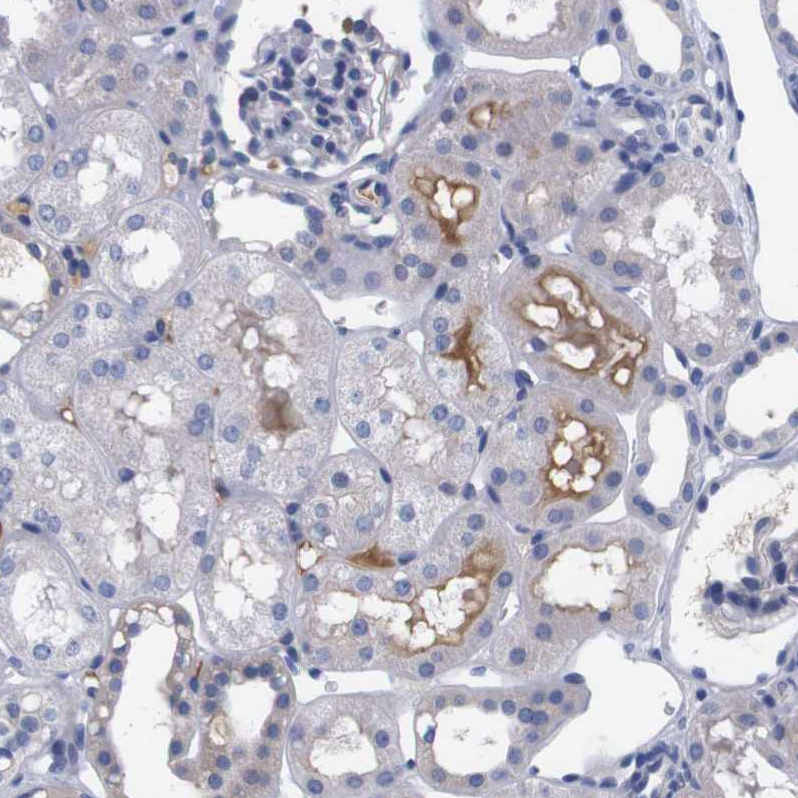

Immunohistochemical staining of human cerebral cortex shows strong cytoplasmic positivity in glial cells.